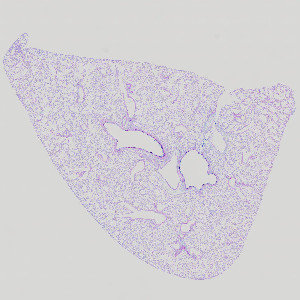

Rodent, Pulmonary MCM, AB-PAS

Pulmonary mucous cell metaplasia (MCM) is a remodeling process where bronchial epithelial cells undergo metaplasia to mucous cells. This causes an increased production of mucous, which leads to increased airway obstruction. Mucous cell metaplasia is often observed as a feature of allergic airways disease (e.g. asthma) after exposure to an allergen (e.g. house dust mites). The mucosubstances in the epithelium are identified by staining with Alcian Blue (pH 2.5)/Periodic Acid-Schiff (AB/PAS or AB-PAS). Using this APP the degree of mucous cell metaplasia is quantified in pulmonary bronchioles as the volume of mucosubstances per length of basal lamina.

Figure 1

Rodent lung after exposure to house dust mite (HDM), stained with AB/PAS.